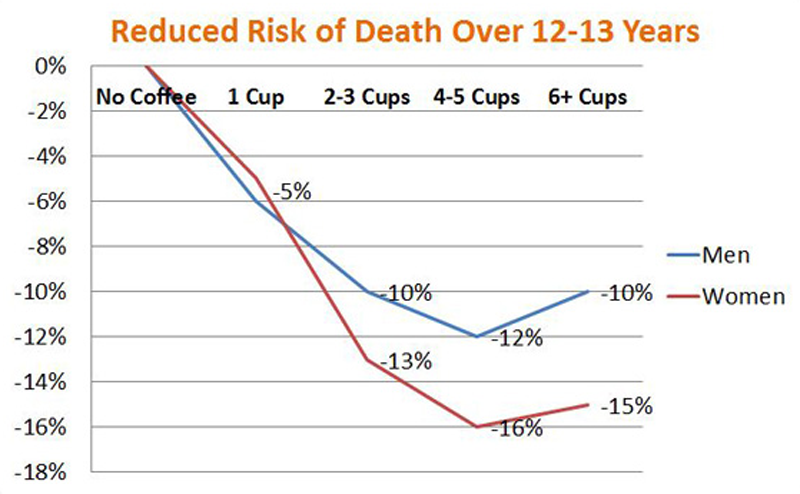

7. Selain kafein, ada banyak zat-zat lainnya dalam kopi yang mungkin baik untuk kesehatan Anda

Itu karena kopi juga mengandung ratusan senyawa yang berbeda. Terdapat banyak antioksidan yang melindungi tubuh kita dari bahan kimia perusak yang disebut "radikal bebas." Molekul-molekul ini menyebabkan penuaan dan berkaitan dengan penyakit seperti kanker dan penyakit jantung. Penelitian NIH menunjukkan bahwa peminum kopi memiliki risiko penurunan Alzheimer, Parkinson, diabetes tipe 2 dan penyakit lainnya.

Untuk diketahui: Pada kenyataannya, banyak peminum kopi juga perokok berat, peminum (miras) berat dan pemakan daging, yang mana semua itu termasuk yang merugikan kesehatan Anda.

Ini berarti bahwa data di atas disesuaikan dengan faktor-faktor risiko, sehingga Anda harus menghindari kebiasaan ini (rokok, alkohol, dan daging) jika Anda ingin kopi memiliki efek positif. Selain itu, penelitian di sini adalah tidak cukup meyakinkan untuk membuktikan hubungan sebab akibat, tapi data terbaik yang kita miliki sejauh ini (atau masih butuh adanya riset lanjutan).

Secara keseluruhan, itu berita baik bagi pecinta kopi!

Itu karena kopi juga mengandung ratusan senyawa yang berbeda. Terdapat banyak antioksidan yang melindungi tubuh kita dari bahan kimia perusak yang disebut "radikal bebas." Molekul-molekul ini menyebabkan penuaan dan berkaitan dengan penyakit seperti kanker dan penyakit jantung. Penelitian NIH menunjukkan bahwa peminum kopi memiliki risiko penurunan Alzheimer, Parkinson, diabetes tipe 2 dan penyakit lainnya.

Untuk diketahui: Pada kenyataannya, banyak peminum kopi juga perokok berat, peminum (miras) berat dan pemakan daging, yang mana semua itu termasuk yang merugikan kesehatan Anda.

Ini berarti bahwa data di atas disesuaikan dengan faktor-faktor risiko, sehingga Anda harus menghindari kebiasaan ini (rokok, alkohol, dan daging) jika Anda ingin kopi memiliki efek positif. Selain itu, penelitian di sini adalah tidak cukup meyakinkan untuk membuktikan hubungan sebab akibat, tapi data terbaik yang kita miliki sejauh ini (atau masih butuh adanya riset lanjutan).

Secara keseluruhan, itu berita baik bagi pecinta kopi!